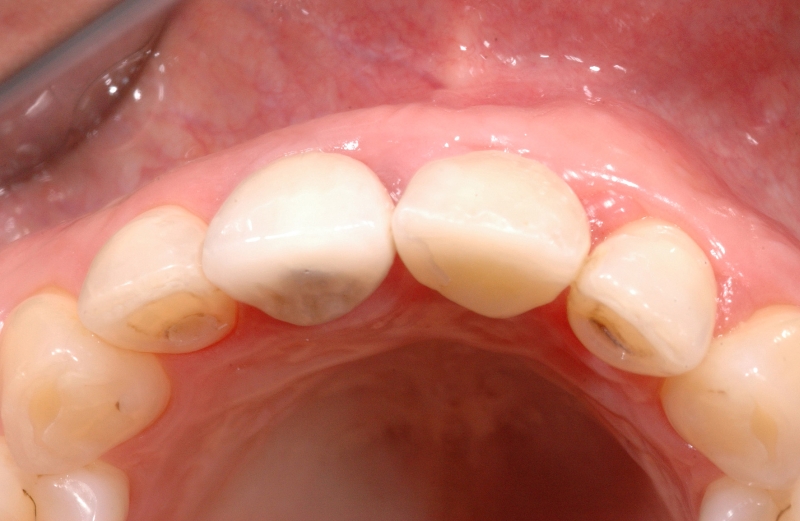

3/18 - Clinical situation 6-8 weeks after extraction, vestibular viewGBR together with soft tissue augmentation with mucoderm® and maxresorb® - Dr. S. Scherg

4/18 - Clinical situation, occlusal viewGBR together with soft tissue augmentation with mucoderm® and maxresorb® - Dr. S. Scherg